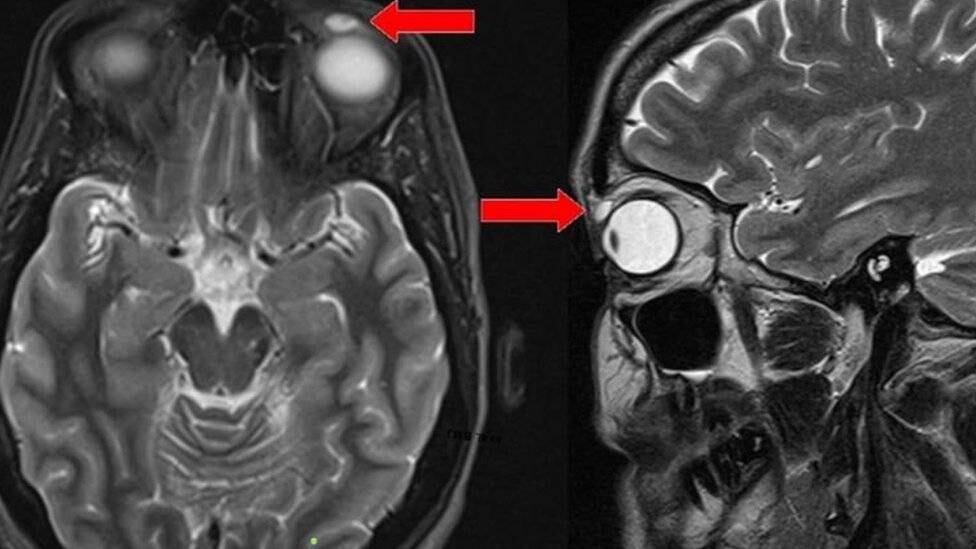

Los investigadores del hospital de Ninewell le realizaron una resonancia magnética, después de que el médico de cabecera de la paciente la remitiera al departamento de Oftalmología.

Las imágenes de la resonancia revelaron un quiste con forma ovoide de unos 8mm de longitud, pero no había evidencia de que hubiese algo dentro.

Cuando los cirujanos extirparon el bulto que había provocado la hinchazón, el quiste se rompió revelando el lente.